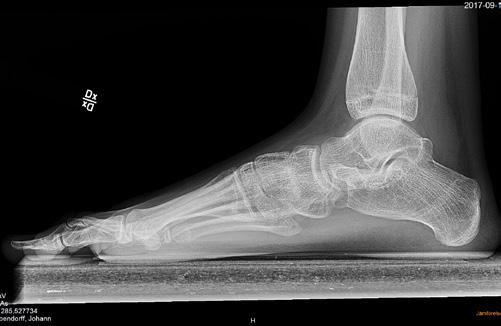

Sannolikt normalt/fysiologiskt hos barn om den är bilateral. Plattfothet undersöks bäst bakifrån när barnet står på hela foten och sedan ställer sig på tå. Då ser man hur bakfoten går från valgus vid belastning till varus vid tåstående. Likaså kan man se att det utvecklas ett längsgående medialt fot valv när barnet ställer sig på tå jämfört med när hela foten belastas. Se bild 1.

Sannolikt. Plattfotheten beror nog mest på flexibla fötter som inte har något strukturellt fel. Observera att det normala är bilateral plattfothet. Unilat eral betyder att en fot är platt, pes plano valgus, eller att den andra är i varus, ibland cavo varus, vilket inte är normalt. Om det finns en tydlig asym metri och fotfelställningen är förvärvad behöver man tänka på möjlig neuropati eller pro cess i spinalkanalen. Se bild 2.

Plattfothet är en felställning i första hand och inte en diag nos. En individuell bedömning av var felställningen sitter och vad den kan bero på behövs. Se bild 3.

Den typiska stortåfelställningen (se bild 1) orsakas av en muskelobalans, som måste korrigeras tillsammans med stortåkirurgin för att resultatet ska bli bestående.